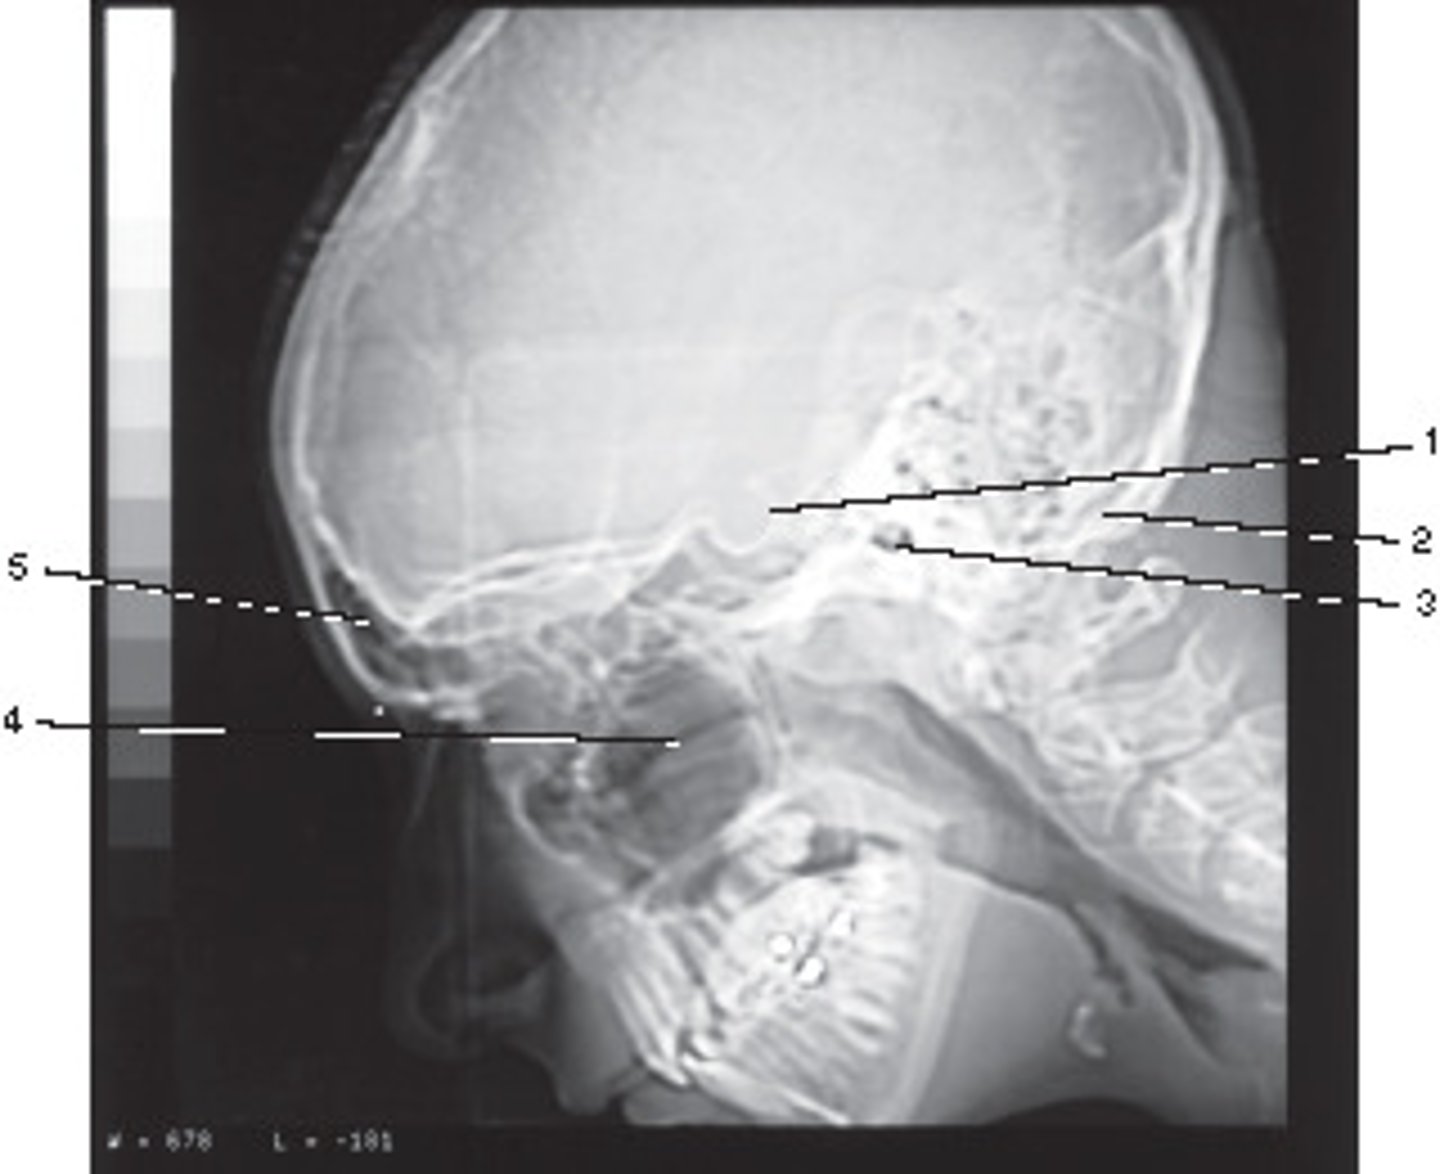

Sagittal

What anatomic plane best describes this image

<p>What anatomic plane best describes this image</p>

Sphenoid sinus

Identify structure B on this sagittal reformat of the occipital bone.

<p>Identify structure B on this sagittal reformat of the occipital bone.</p>